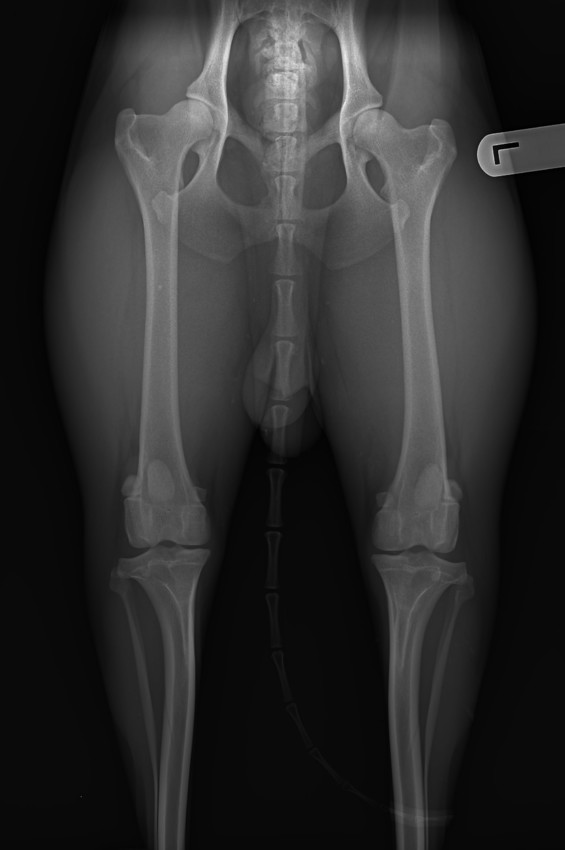

Met HD B heupen kan je prima verantwoord fokken. Het verschil tussen A en B heupen op een foto:

Ben benieuwd of je bij deze 2 foto's kunt zien welke de A en welke de B heupen zijn.....

De eerste zijn de B heupen, de tweede de A heupen? Bij de eerste lijkt de heupkom minder diep dan bij de tweede.

Klopt helemaal, de diepte van de heupkommen is inderdaad het verschil.